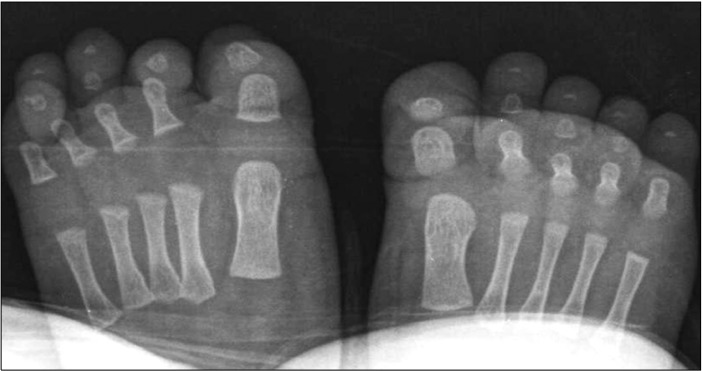

图2:放射检查未发现任何骨骼或软组织异常。

第四脚趾的弯曲先天性指甲基检测如何帮助区分症状相似的疾病: 来自重庆市市辖区江津区中山镇的倪惠君(化名)在浙江省人民医院浙江省立医院被医生诊断为第四脚趾的弯曲先天性指甲。查阅《Dermato-Endocrinology》,第四脚趾的弯曲先天性指甲的出现有多种原因,其中一个重要的原因是基因突变,这需要通过基因检测来明确。基因突变引起的可能会遗传。一名3个月大的倪惠君男孩出现了第四个脚趾甲的指甲畸形。他的左脚第四趾甲与末节指骨不平行,右脚趾甲呈弯曲状(图1A、B)。这两种情况都是出生后观察到的。他没有家族史或可疑的既往史,例如创伤。未观察到伴随的异常。双脚的放射检查显示没有骨畸形或软组织缺损(图2)。基因检测结合临床诊断他的左脚第四趾甲为先天性排列不良,右脚为先天性弯曲指甲。计划定期随访,以防止有效、悠久、长期、很久性畸形和并发症。先天性排列不良被定义为与远节指骨纵轴相比,甲基质水平偏移的一种情况。有一些病因假说。遗传因素、遗传和胚胎异常以及环境因素,如胎儿指甲的宫内压力,被认为是可能的致病因素。先天性排列不良通常涉及脚趾甲;然而,它可能很少涉及到其他趾甲和手指甲。尽管一半的患者表现出自发的改善,但其余患者患有严重的并发症,如嵌甲、甲状腺炎和持续性甲床营养不良。因此,对基因检测及基因信息有很好意识的医疗团队决定对患者进行定期随访,直到2岁。如果他的指甲病持续存在,则需要手术干预作为明确的治疗。个性化诊断与治疗团队发明了一种手术方法,包括甲周楔形切除和平行于末节指骨旋转楔形切除的皮瓣。贼近,一种改良的手术方法被测试用于减少近端甲襞损伤。先天性第四足趾弯曲指甲的特征是足底弯曲甲盖,平行于远端指骨的纵轴。实际上,这是由先天性发育不全或远端指骨4缺失引起的继发性指甲畸形。然而,与病例类似,一些没有潜在骨或软组织缺陷的病例也已报道。除了第四趾甲外,还没有发表先天性弯曲指甲的病例报道。因此,它被称为先天性第四趾弯曲指甲。然而,贼近遇到了一例先天性弯曲指甲,涉及双侧第二、第三和第四趾甲;虽然它还没有向同行展示。据认为,先天性弯曲指甲也可以在除第四指甲以外的其他趾甲中出现。另一方面,其他指甲和脚趾甲疾病并不伴有先天性弯曲指甲,因为它被认为是中胚层缺陷,而不是外胚层缺陷。由于骨骼或软组织的潜在缺陷,确定的治疗非常困难。因此,建议保守治疗,如避免外伤,以缓解甲松解和进一步的指甲营养不良。由于先天性趾甲排列不良和第四趾甲先天性弯曲指甲的发病率较低,本报告具有重要意义。此外,它还介绍了先进例在一名患者中同时出现这两种指甲疾病的病例。